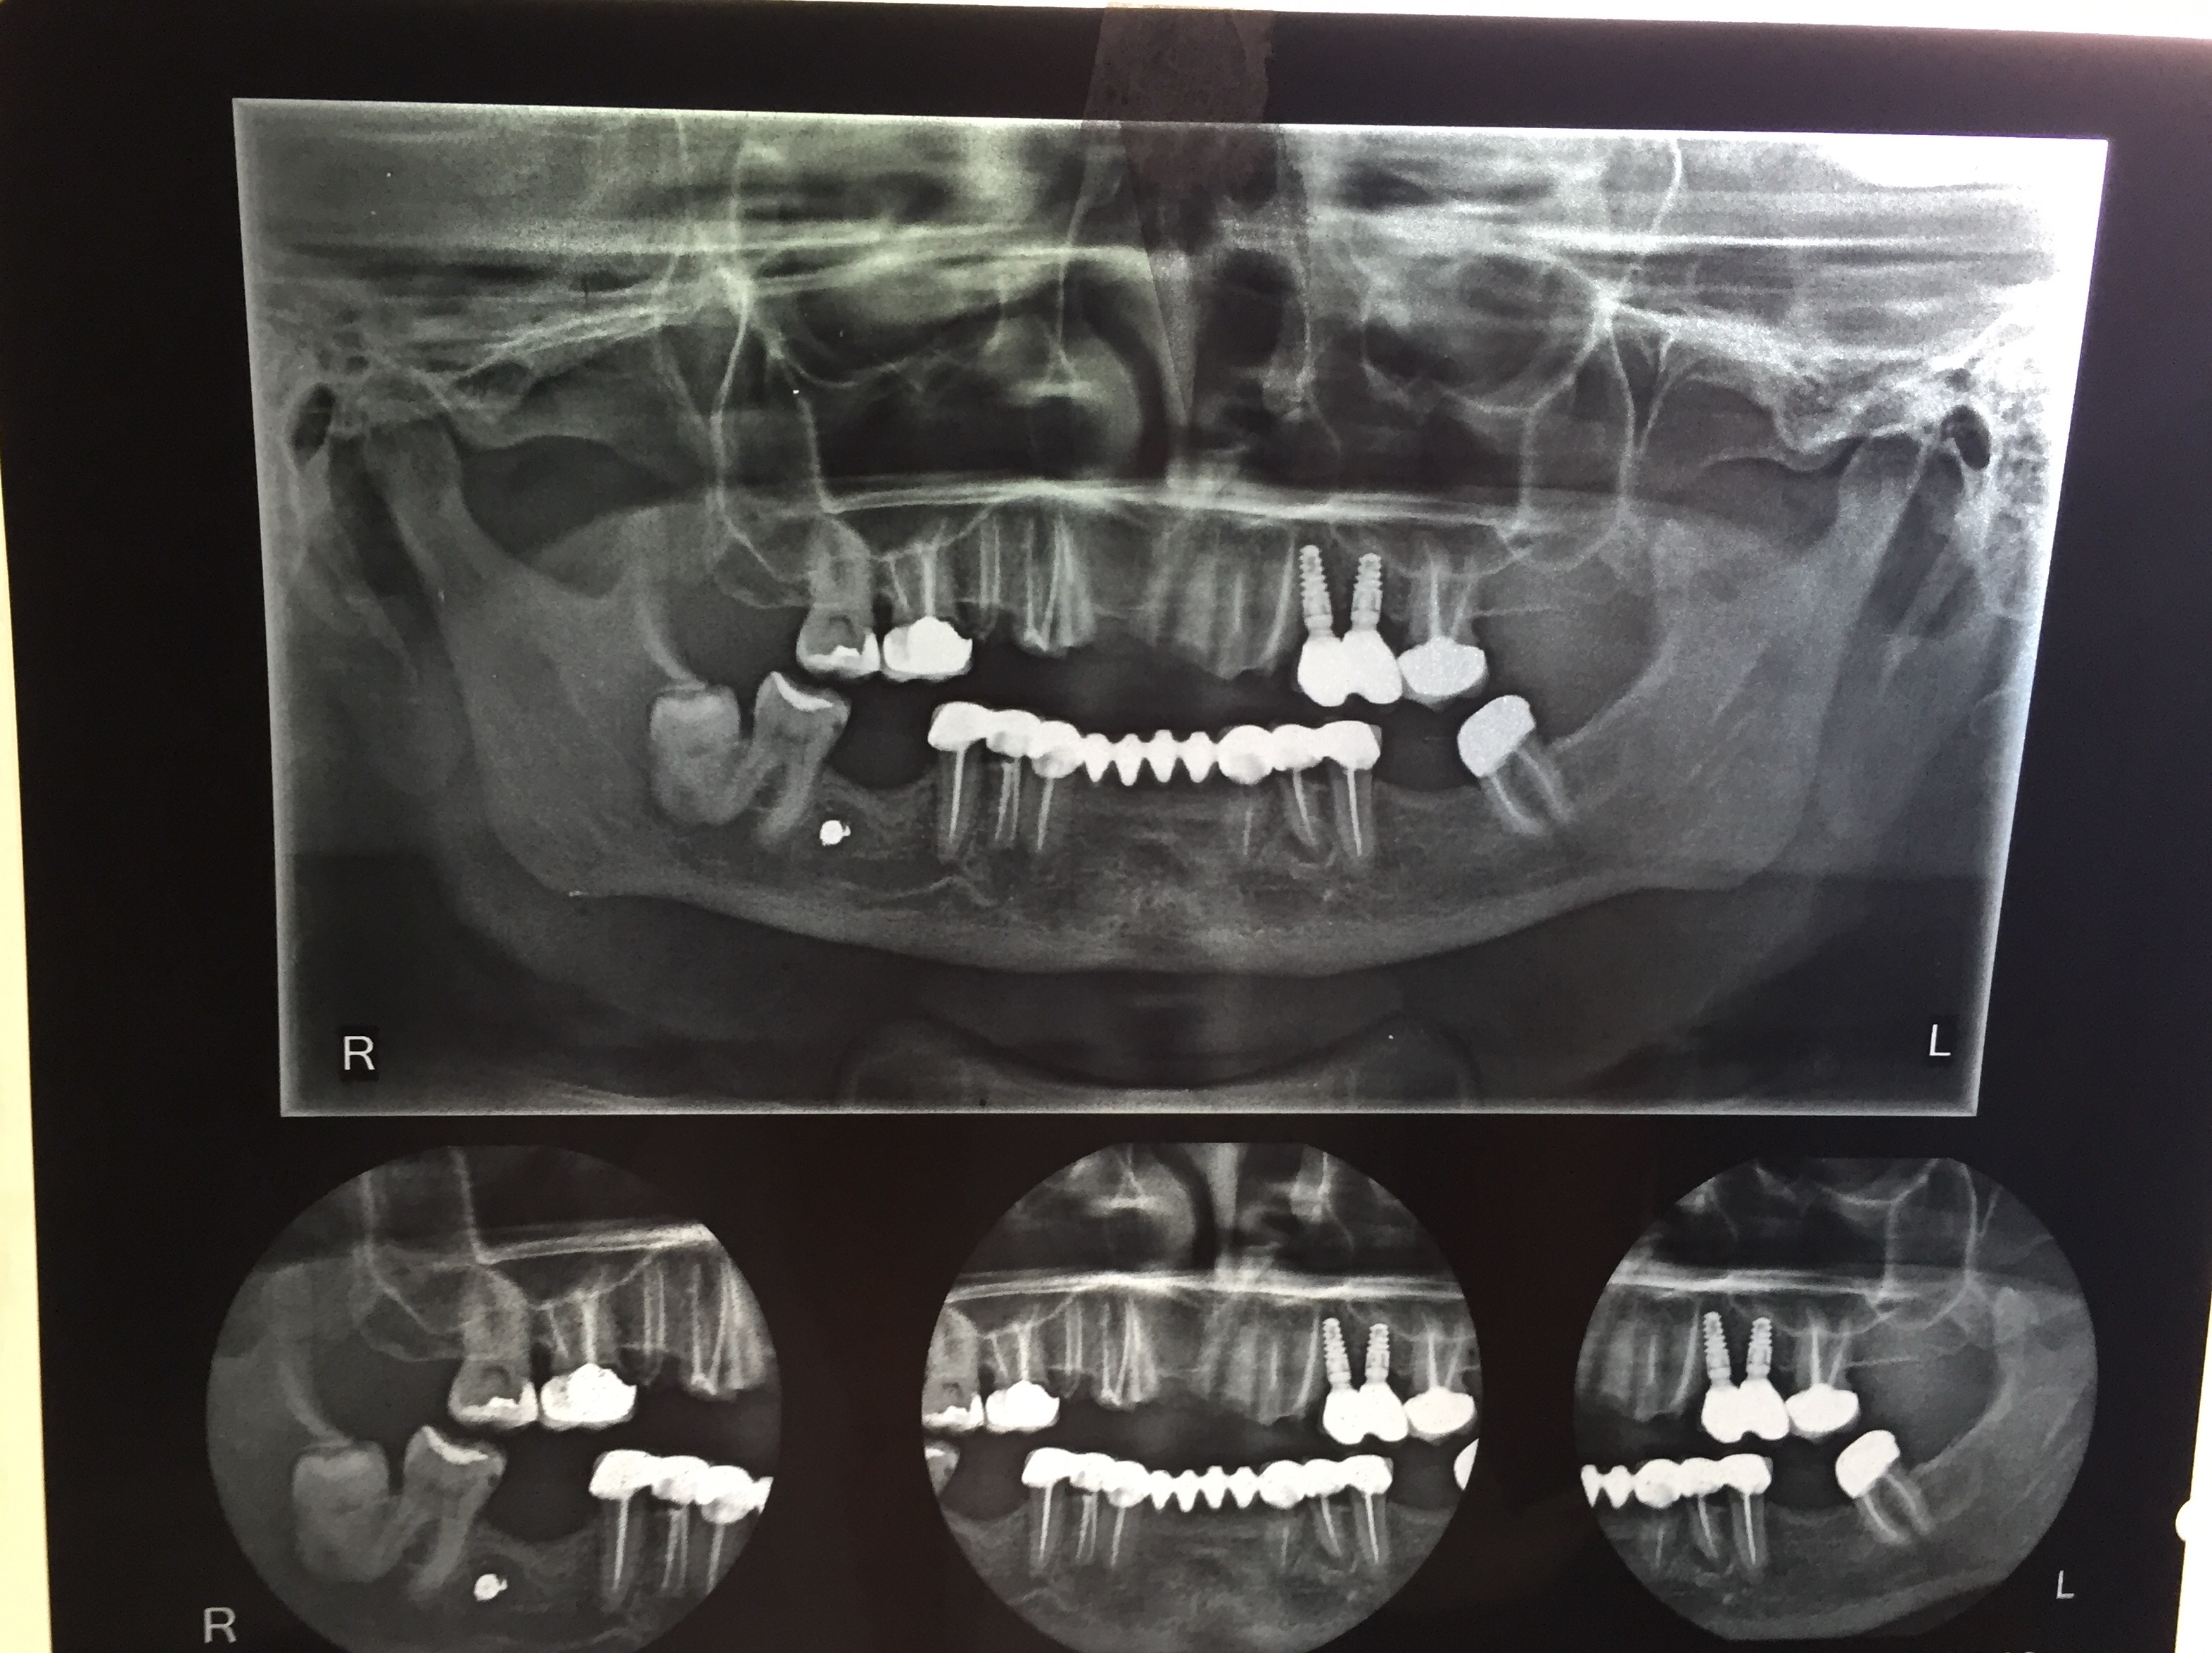

Upper Jaw Full Mouth Implants with Immediate Crowns